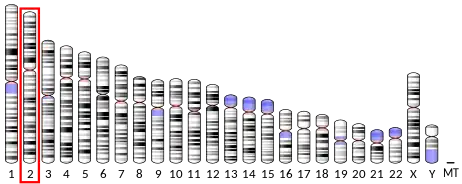

DNA mismatch repair protein Msh2 also known as MutS homolog 2 or MSH2 is a protein that in humans is encoded by the MSH2 gene, which is located on chromosome 2. MSH2 is a tumor suppressor gene and more specifically a caretaker gene that codes for a DNA mismatch repair (MMR) protein, MSH2, which forms a heterodimer with MSH6 to make the human MutSα mismatch repair complex. It also dimerizes with MSH3 to form the MutSβ DNA repair complex. MSH2 is involved in many different forms of DNA repair, including transcription-coupled repair,[5] homologous recombination,[6] and base excision repair.[7]

Mutations in the MSH2 gene are associated with microsatellite instability and some cancers, especially with hereditary nonpolyposis colorectal cancer (HNPCC). At least 114 disease-causing mutations in this gene have been discovered.[8]

Hereditary nonpolyposis colorectal cancer (HNPCC), sometimes referred to as Lynch syndrome, is inherited in an autosomal dominant fashion, where inheritance of only one copy of a mutated mismatch repair gene is enough to cause disease phenotype. Mutations in the MSH2 gene account for 40% of genetic alterations associated with this disease and is the leading cause, together with MLH1 mutations.[9] Mutations associated with HNPCC are broadly distributed in all domains of MSH2, and hypothetical functions of these mutations based on the crystal structure of the MutSα include protein–protein interactions, stability, allosteric regulation, MSH2-MSH6 interface, and DNA binding.[10] Mutations in MSH2 and other mismatch repair genes cause DNA damage to go unrepaired, resulting in an increase in mutation frequency. These mutations build up over a person's life that otherwise would not have occurred had the DNA been repaired properly.